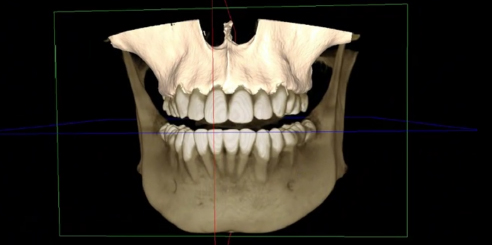

To begin with, the Dental CBCT by LargeV delivers advanced AI-powered 3D imaging and panoramic X-ray designed for accurate dental diagnostics and treatment planning.

It ensures detailed visualization of oral structures while keeping radiation exposure low and image quality high.

The LargeV CBCT supports CT, CEPH, and panoramic imaging in one compact system.

It delivers sharp, high-contrast images that reveal every dental structure with exceptional clarity.

The system achieves image resolutions up to 2.0 lp/mm with a voxel size range of 0.05 – 0.25 mm.

Furthermore, the high-definition image output ensures accurate diagnosis and confident treatment planning.